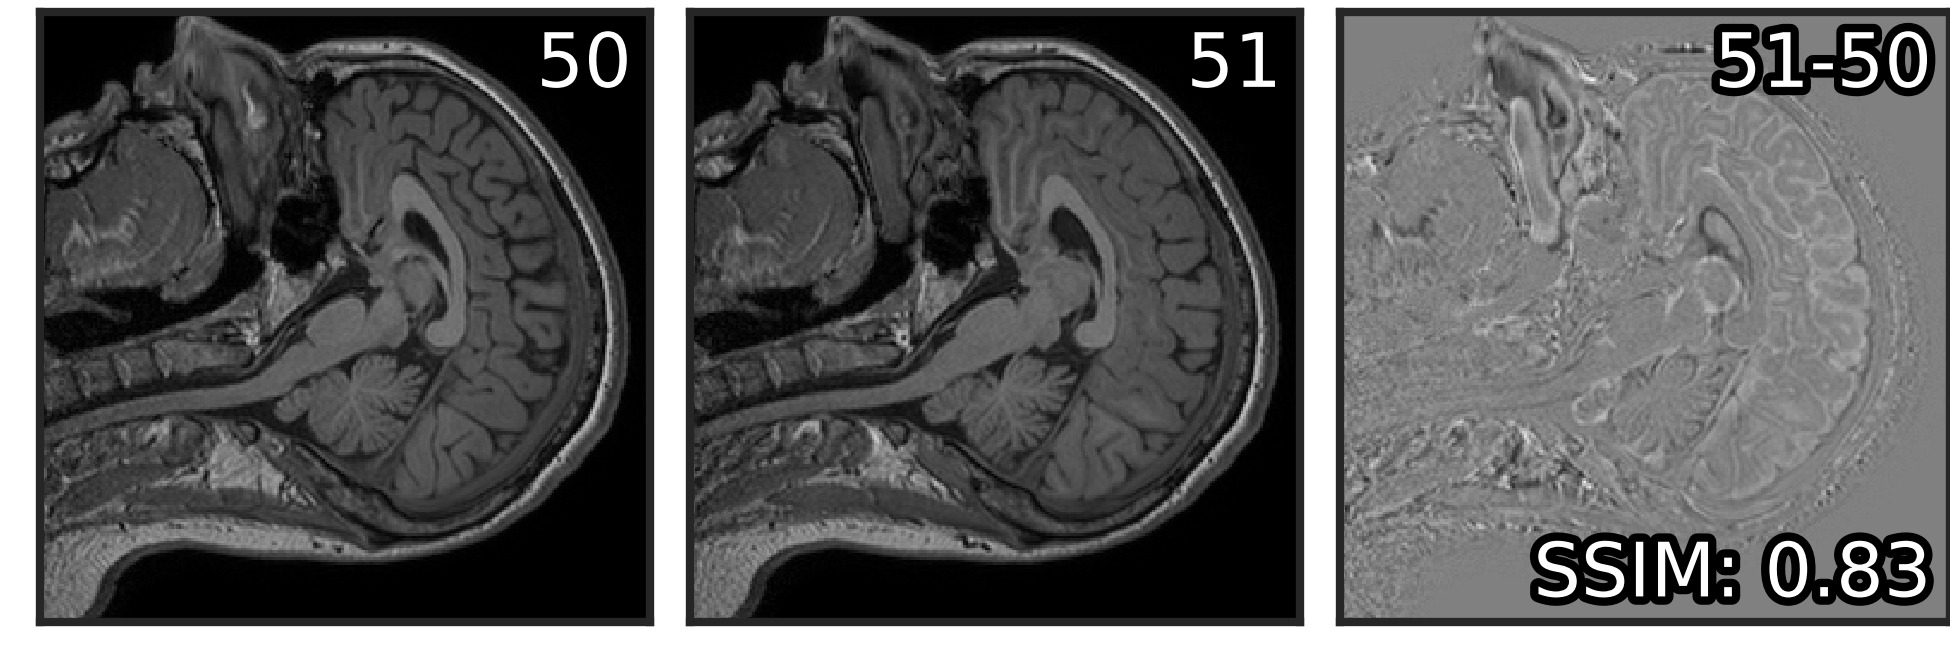

The Noise2Stack method was inspired by the observation of neighboring plane similarity in a number of volumetric biomedical datasets (Figure 1). For example, for MRI brain scan dataset that we used in our experiments (Section 2.2), the average structural similarity between neighboring planes is . We showed that U-Net is able to capture this mutual information and effectively use it for denoising. In both copy-supervised (where original Noise2Noise belongs) and self-supervised modes, two neighbors from each side (four total) were optimal for denoising of MRI. Two neighbors, one from each side, were best for the fluorescent microscopy. Adding more neighbors to the stack did not affect the performance in copy-supervised mode and made it slightly worse for self-supervised mode, where only neighbors were used as the network’s input. We hypothesize that this effect depends on the physical distance between imaged planes, and that the optimal number of planes differs between datasets. However, it is clear that further planes provide less useful information for the restoration and could lead to network overfitting.

Visually, the level of detail in MRI denoised with Noise2Stack in copy-supervised mode has noticeably increased comparing to Noise2Noise, as can be seen in Figure 3 (additional illustrations provided in Supplementary material, Figure S1). Brain gyri in the reconstructed images are clean and sharp even for the cerebellum where they are tiny. In self-supervised mode Noise2Stack results are expectedly less detailed and match Noise2Noise by sight. However, this mode demands twice less data, being able to learn from a single copy. For the fluorescent microscopy, Noise2Stack in self-supervised mode did not outperform supervised Noise2Clean, but has shown comparable results.